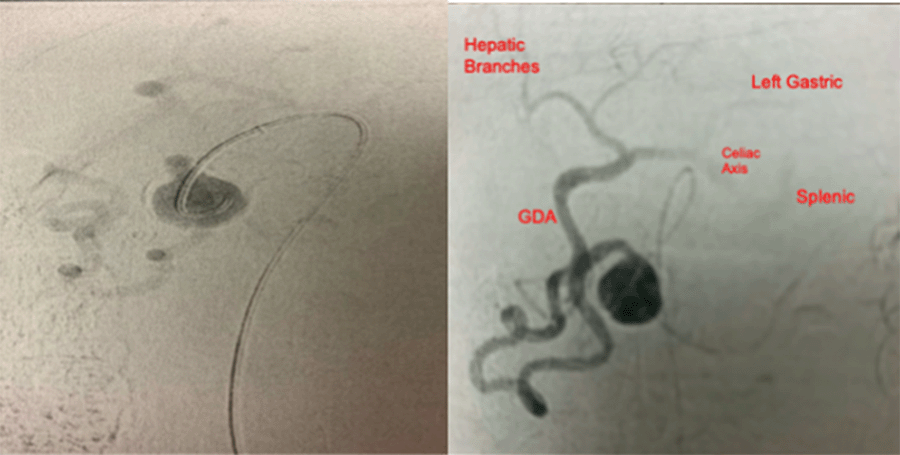

In a hybrid operative suite, access was obtained through the right common femoral artery under ultrasound guidance in a retrograde manner with 5F sheath placement. There was conversion to 6F RDC Destination Terumo sheath (Terumo Medical Corporation, Tokyo, Japan). An aortogram was initially performed in which celiac occlusion was observed directly off its origin. Then, selective SMA first-order arteriography was performed and revealed a calcified arterial segment of the SMA with inflow and outflow through the aneurysm. The outflow vessel then filled the GDA, hepatic, gastric and splenic vessels in a retrograde fashion, which was attributed to the celiac occlusion; the procedure was aborted due to these findings (Figure 2). As previously discussed, she was then admitted to the hospital for open preoperative planning. Vein mapping was completed before OR. An exploratory laparotomy was performed with mobilization of the duodenum to obtain proximal and distal control of the aneurysmal segment (Figure 3). The segment was excised, and an interposition bypass was performed utilizing the greater saphenous vein in an end-to-end fashion with 6-0 Prolene (Figure 4). Adequate flow was ensured distally with palpation and doppler signal. Her abdomen was closed in the usual fashion without drain placement. Final pathology reported a mesenteric arterial aneurysm, 3.5 × 2.5 × 2.4 cm overall, with moderate atherosclerosis and dystrophic calcification (Figure 5). The patient was discharged on postoperative day six. She had returned to work and daily activity without back pain by her two-week follow-up appointment.

Figure 2. Pre-arteriogram Catheterization of SMA Aneurysm and Subsequent Runoff Revealing Retrograde Filling Secondary to Celiac Occlusion. Published With Permission